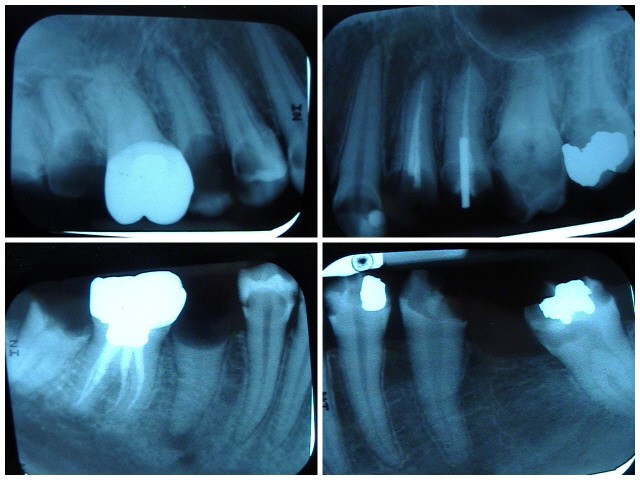

The patient in Figure 10 through Figure 12 was pregnant when she presented for dental treatment. The pregnancy was unplanned and she had had a lack of prenatal care. Continuing meth use during the pregnancy resulted in a positive toxic baby. She stated that she had just stopped using meth and had entered a rehabilitation facility a few days before. She was brought to the author’s clinic with a toothache. Note that as seen in these images, extreme accumulation of plaque, lack of oral hygiene, and severely decayed and missing teeth are classic manifestations in meth users.

Fig 12. Radiographs of patient in Fig 10 and Fig 11 illustrating nonrestorability of the dentition.

Figure 12